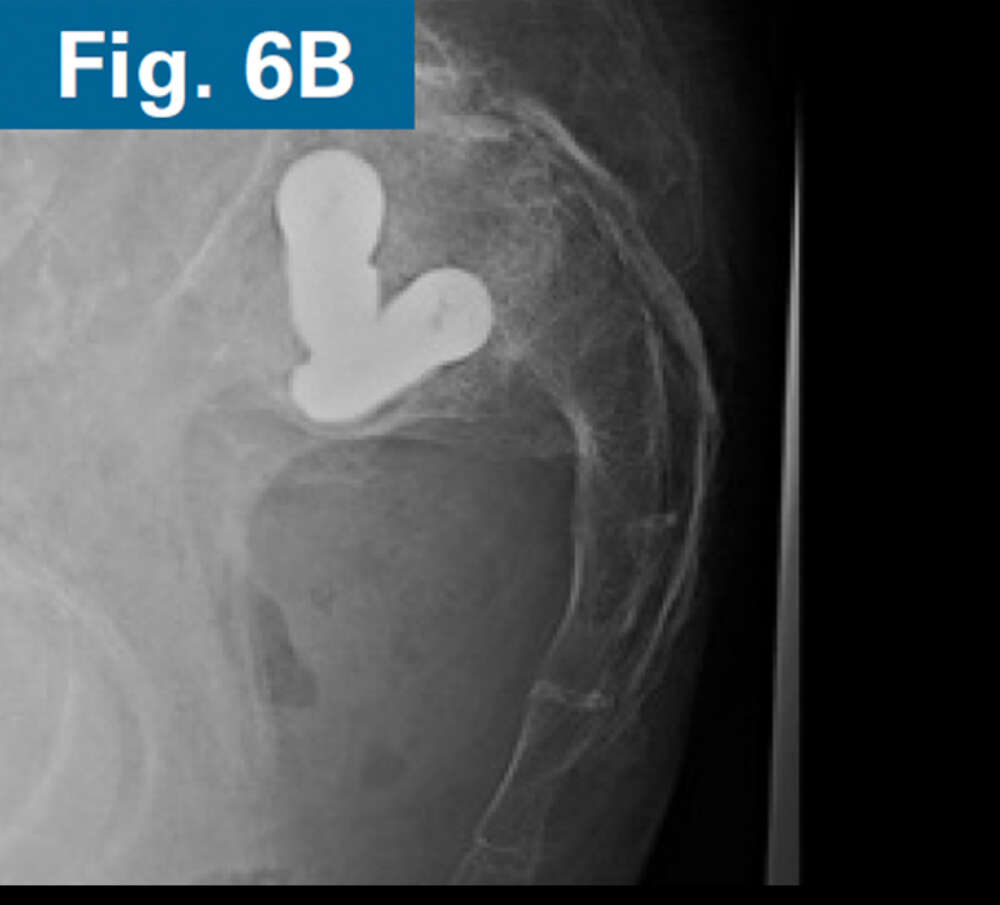

• Immediate postoperative CT scan demonstrate safe placement of implants (Figs. 5A and 5B).

• AP and standing lateral sacral view at 3 months follow-up.

• Callous formation noted on the lateral radiograph (Figs. 6A and 6B).

• Clinically, the patient is ambulating comfortably and is not requiring opioids.4